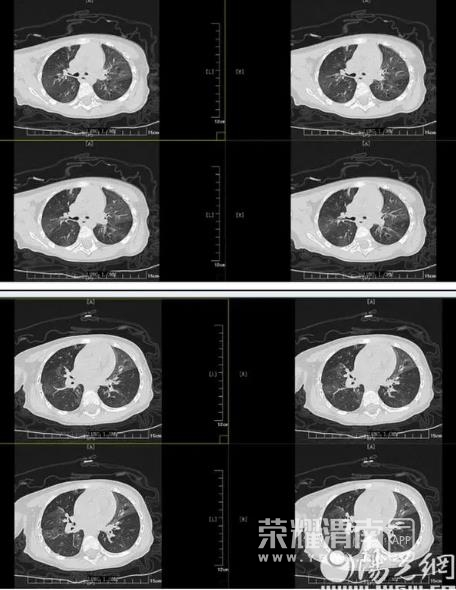

但胸部CT的结果表明小丸子的肺内病变比较重,同时通气也不均匀,确实存在堵塞,可这个"堵住气管的东西”到底是什么,还得在支气管镜检查下才能知道。在和小丸子的父母详细沟通病情后,入院第二天一早,小儿内科田恬主任便为其进行了无痛电子支气管镜检查。

镜下,小丸子的气管壁黏膜十分粗糙,红肿明显,右肺中间支有大量白色黏稠分泌物,遂在检查的同时进行了支气管肺泡灌洗治疗,清除黏稠的分泌物和痰栓,“足足洗出来3管浓稠的奶酪色痰絮”!田恬主任表示。术后,灌洗液被送去化验病原,以便让小丸子后续的抗感染治疗更加精准。